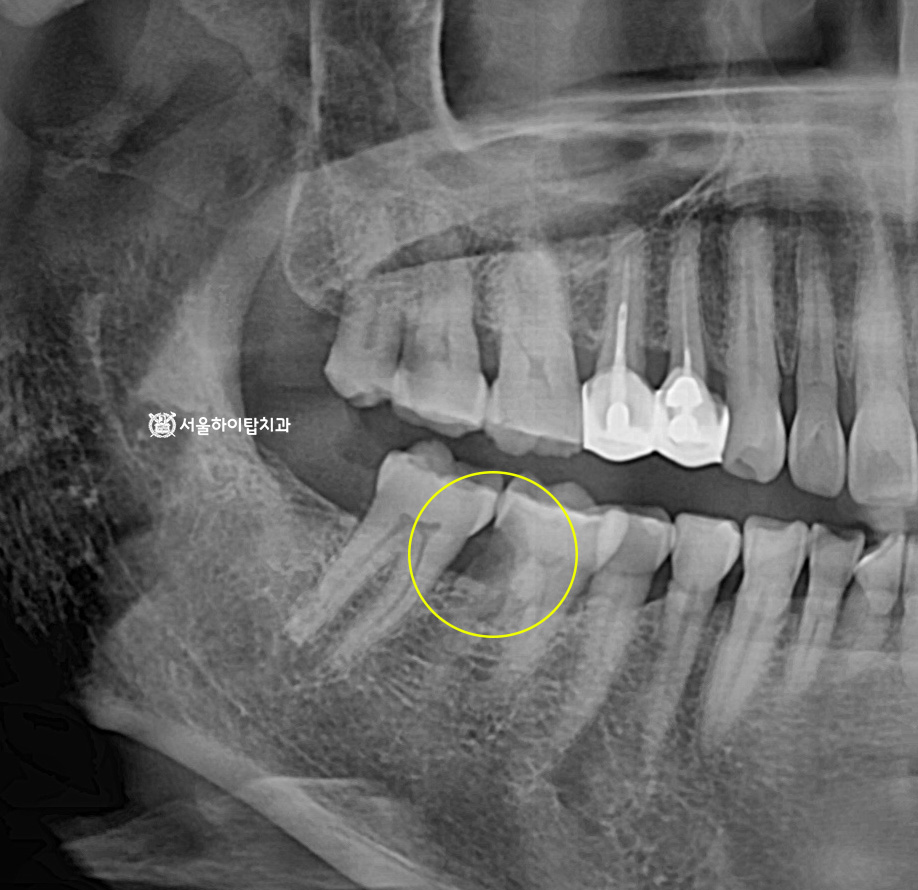

십정동 치과 상실된 치아가 불러오는 연쇄적 문제? 치조골 흡수와 기울어진 어금니, 뼈이식 동반 임플란트 과정 동암역 치과 : 균형 잡힌 저작이 중요한 이유, 전반적으로 손상된 치아 및 잇몸 임플란트를 통해 저작 기능 개선 간석역 치과 치주염으로 인한 치조골 흡수, 치아 파절 및 마모까지 임플란트 가상 시뮬레이션을 통한 안전한 수술 과정 1 2 Next Archives 2026년 4월 2026년 3월 2026년 2월 2026년 1월 2025년 12월 2025년 11월 Categories 미분류 신경치료 심미 치료 임플란트